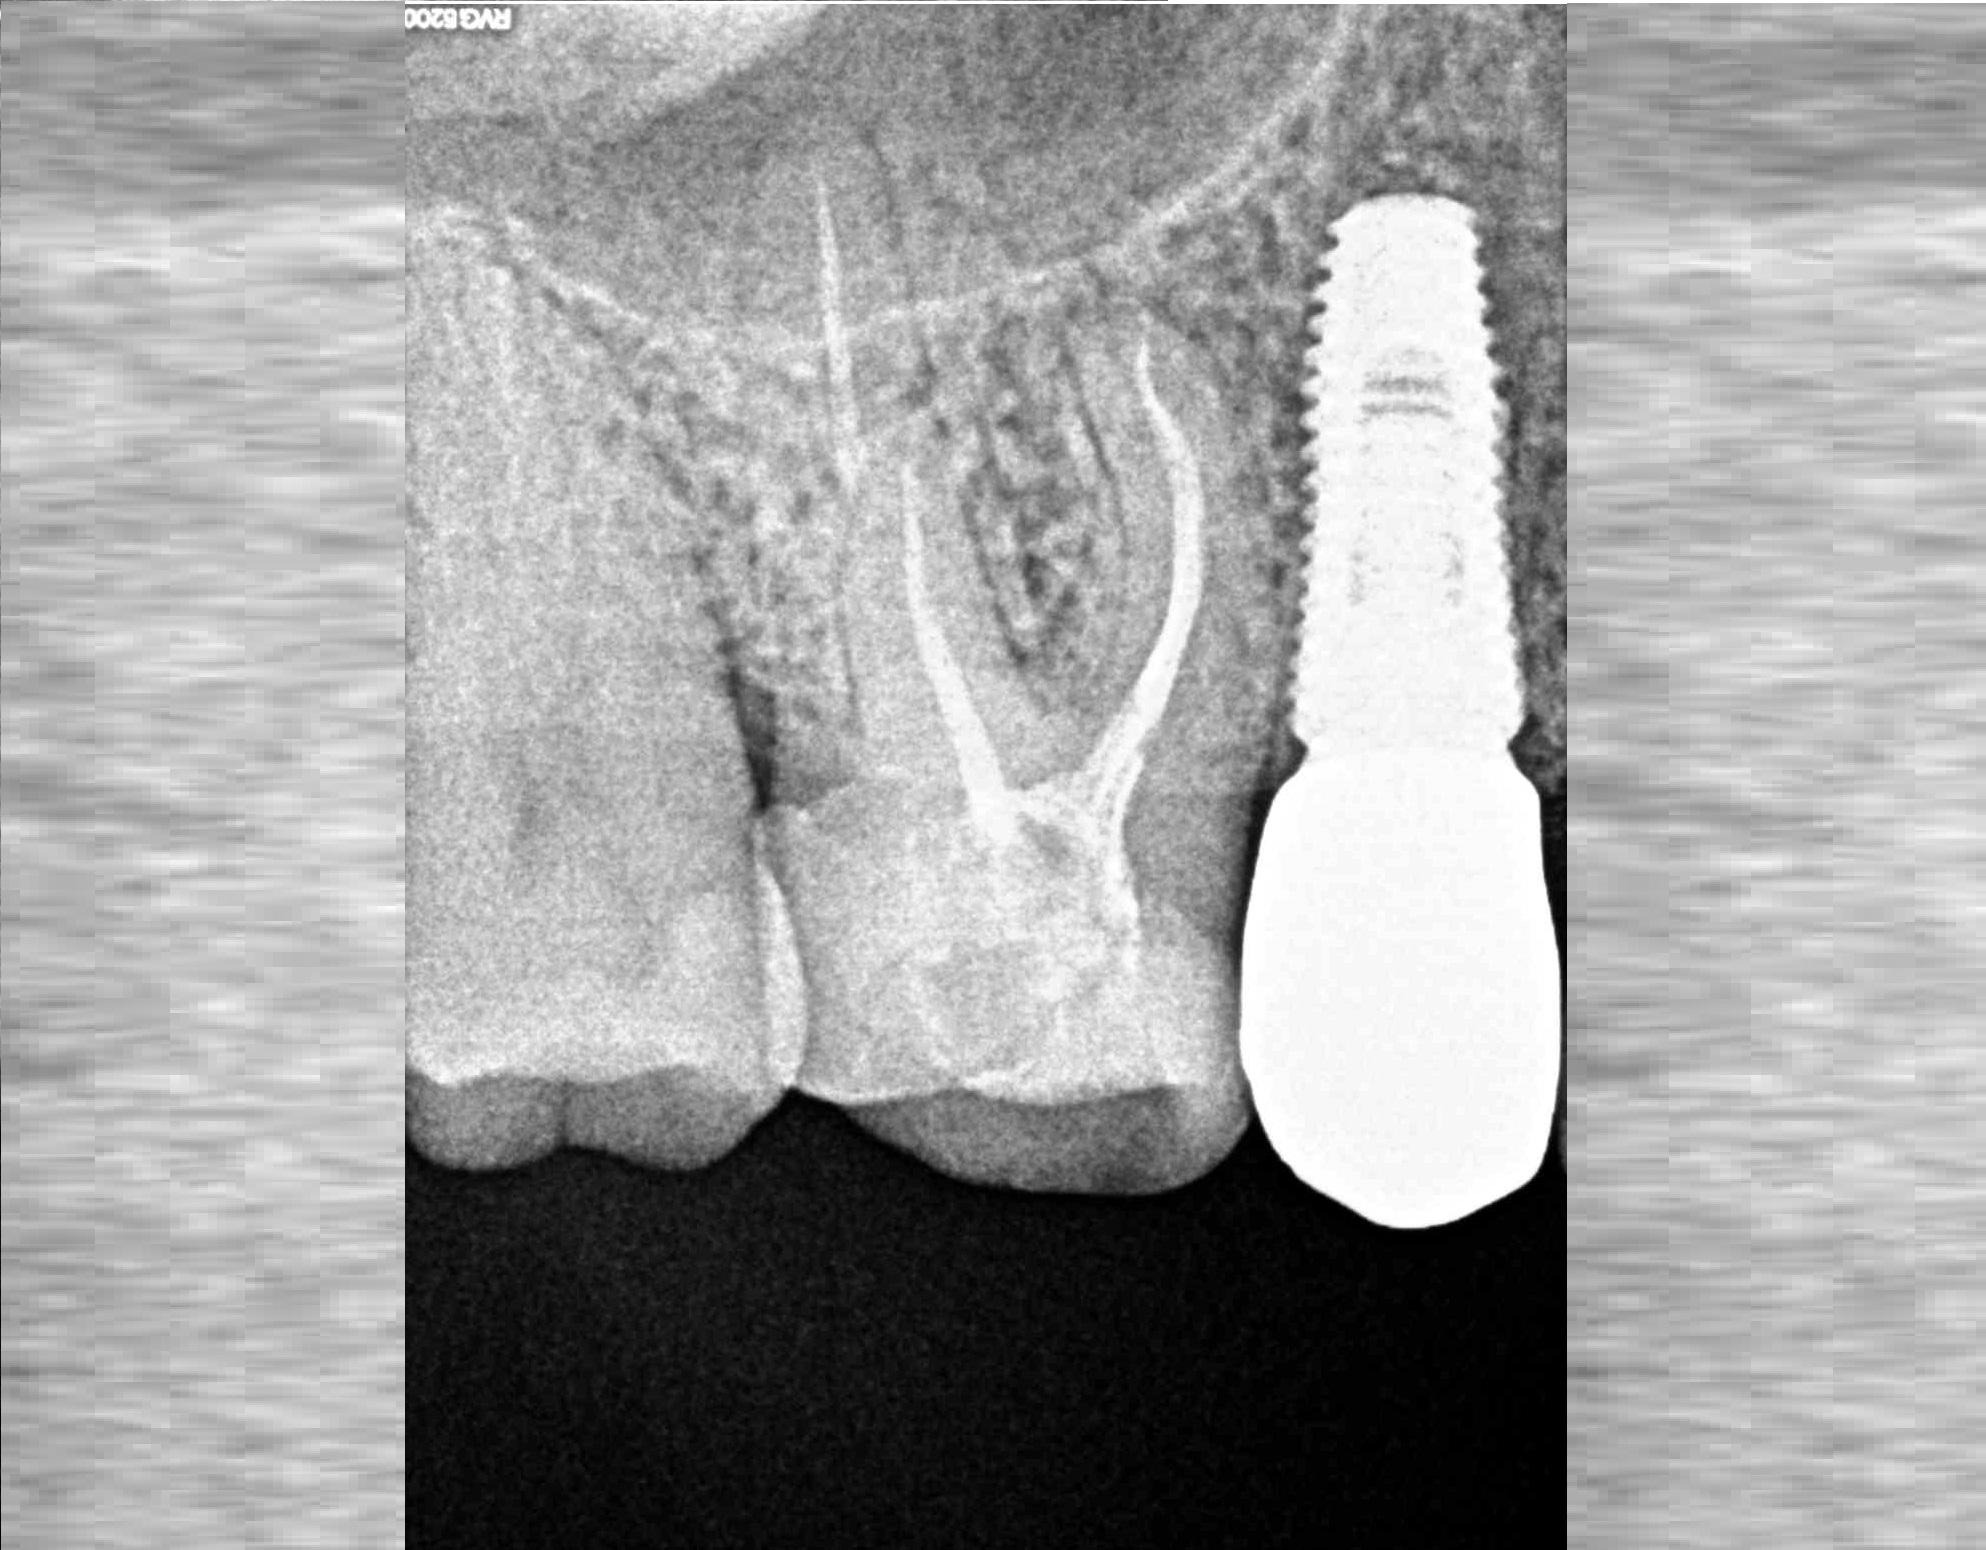

Проблема

Пациент обратился в клинику с постоянными ноющими болями усиливающимися при накусывании.

Решение

В нескольких клиниках было предложено удаление данного зуба. В нашей клинике такие зубы лечат. Пациенту было проведено эндодонтическое лечение данного зуба. Результат положительный, идет восстановление костной ткани.